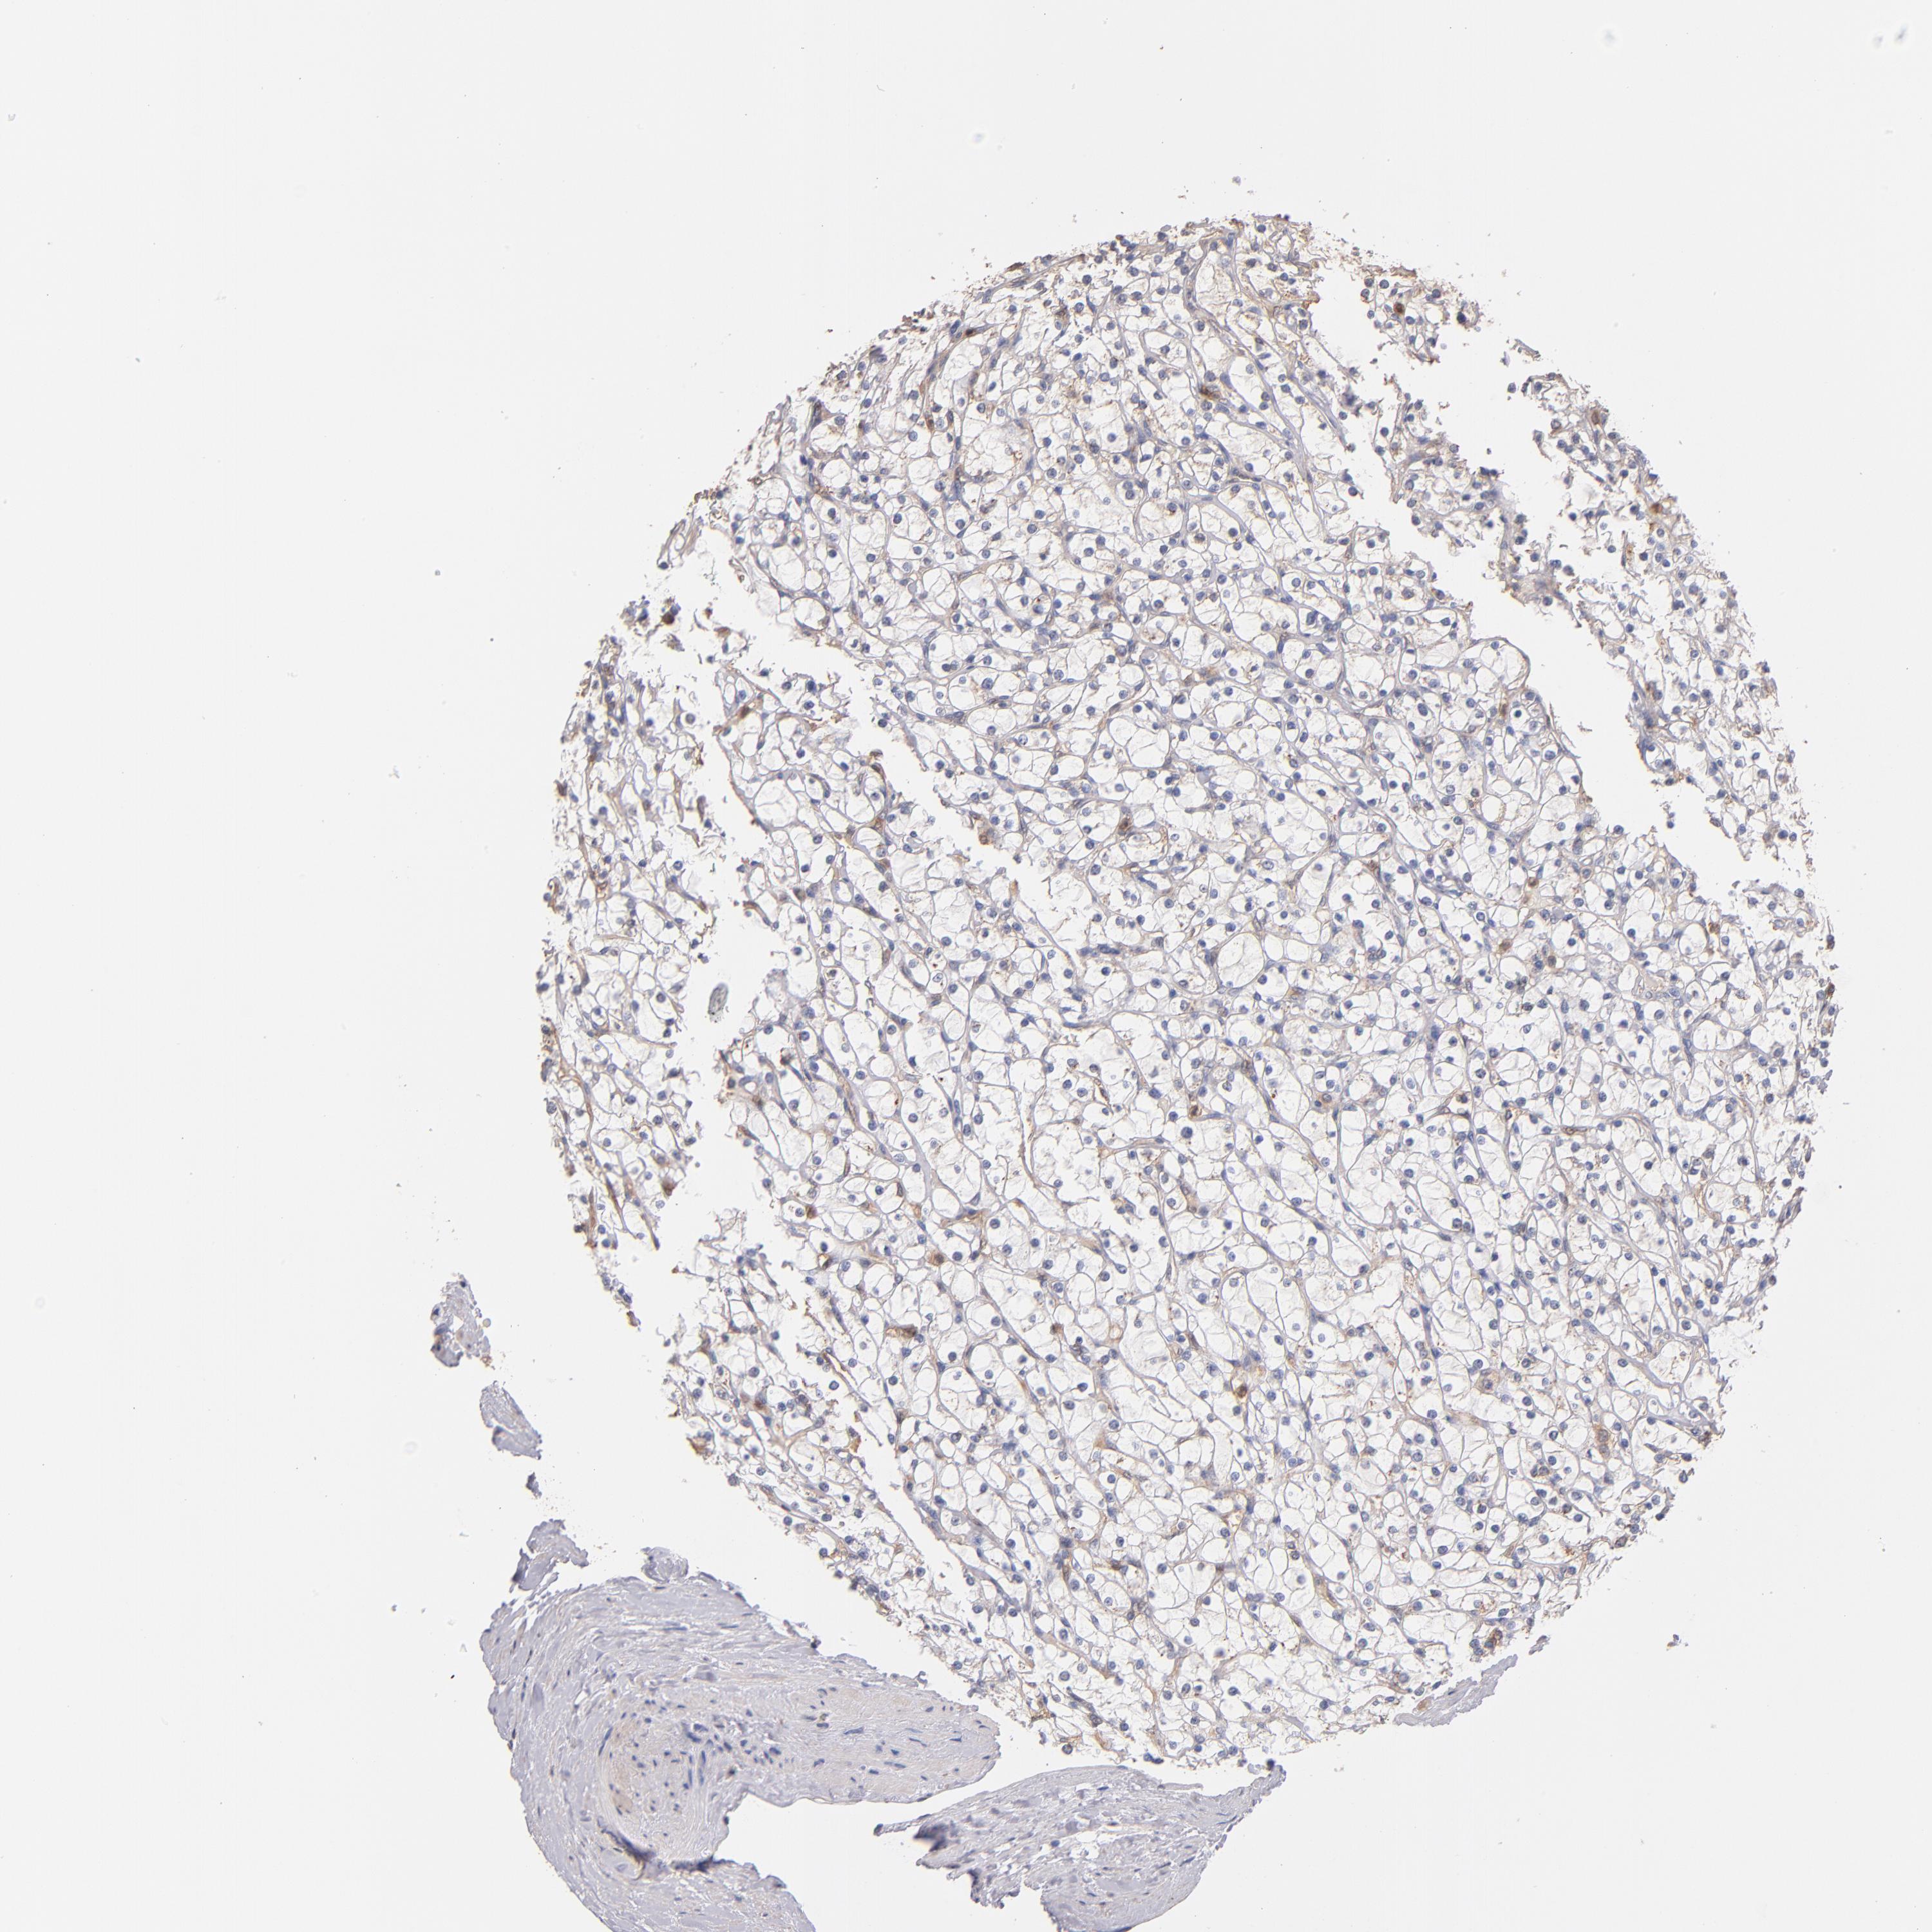

KIDNEY RENAL CLEAR CELL CARCINOMA (VALIDATION) - Interactive survival scatter ploti

The Survival Scatter plot shows the clinical status (i.e. dead or alive) for all individuals in the patient cohort, based on the same data that underlies the corresponding Kaplan-Meier plots. Patients that are alive at last time for follow-up are shown in blue and patients who have died during the study are shown in red.

The x-axis shows the expression levels (FPKM) of the investigated gene in the tumor tissue at the time of diagnosis. The y-axis shows the follow-up time after diagnosis (years). Both axes are complimented with kernel density curves demonstrating the data density over the axes. The top density plot shows the expression levels (FPKM) distribution among dead (red) and alive patients (blue). The right density plot shows the data density of the survived years of dead patients with high and low expression levels respectively, stratified using the cutoff indicated by the vertical dashed line through the Survival Scatter plot. This cutoff is automatically defined based on the FPKM cutoff that minimizes the p-score. The cutoff can be changed by dragging the vertical line or by entering a cutoff value in the square labeled "Current cut-off".

Under the Survival Scatter plot the p-score landscape (black curve; left axis) is shown together with dead median separation (red curve; right axis). Dead median separation is the difference in median mRNA expression between patients who have died with high and low expression, respectively. It is calculated as follows: median FPKM expression of dead patients with high expression - median FPKM expression of dead patients with low expression. This is intended to aid the user in visually exploring custom cutoffs and the associated p-scores and dead median separation.

Individual patient data is displayed and can be filtered by clicking on one or more of the category buttons on the top of the page. Categories describing expression level and patient information include: high, low, alive, dead, female, male and tumor stages. The scale of the x-axis can be toggled between linear and log-scale by clicking on the "x log" button. Mouse-over function shows TCGA ID, patient information and mRNA expression (FPKM) for each patient.

& Survival analysisi

Kaplan-Meier plots summarize results from analysis of correlation between mRNA expression level and patient survival. Patients were divided based on level of expression into one of the two groups "low" (under cut off) or "high" (over cut off). X-axis shows time for survival (years) and y-axis shows the probability of survival, where 1.0 corresponds to 100 percent.

RO60 is not prognostic in Kidney Renal Clear Cell Carcinoma (validation)

Best expression cut offi

Based on the FPKM value of each gene, patients were classified into two groups and association between prognosis (survival) and gene expression (FPKM) was examined. The best expression cut-off refers the FPKM value that yields maximal difference with regard to survival between the two groups at the lowest log-rank P-value. Best expression cut-off was selected based on survival analysis .

When clicking on this number, the vertical dashed line indicating cut-off, the interactive survival plot, and the Kaplan-Meier curve will be adjusted to show results based on the best expression cut-off.

: 13.9

P scorei

Log-rank P value for Kaplan-Meier plot showing results from analysis of correlation between mRNA expression level and patient survival.

N/A

TCGA RNA samplesi

RNA-seq data is reported as average FPKM (number Fragments Per Kilobase of exon per Million reads), generated by the The Cancer Genome Atlas (TCGA) .

Normal distribution across the dataset is visualized with box plots, shown as median and 25th and 75th percentiles. Points are displayed as outliers if they are above or below 1.5 times the interquartile range. FPKM values of the individual samples are presented next to the box plot.

Average pTPM 12.3

Number of samples 100